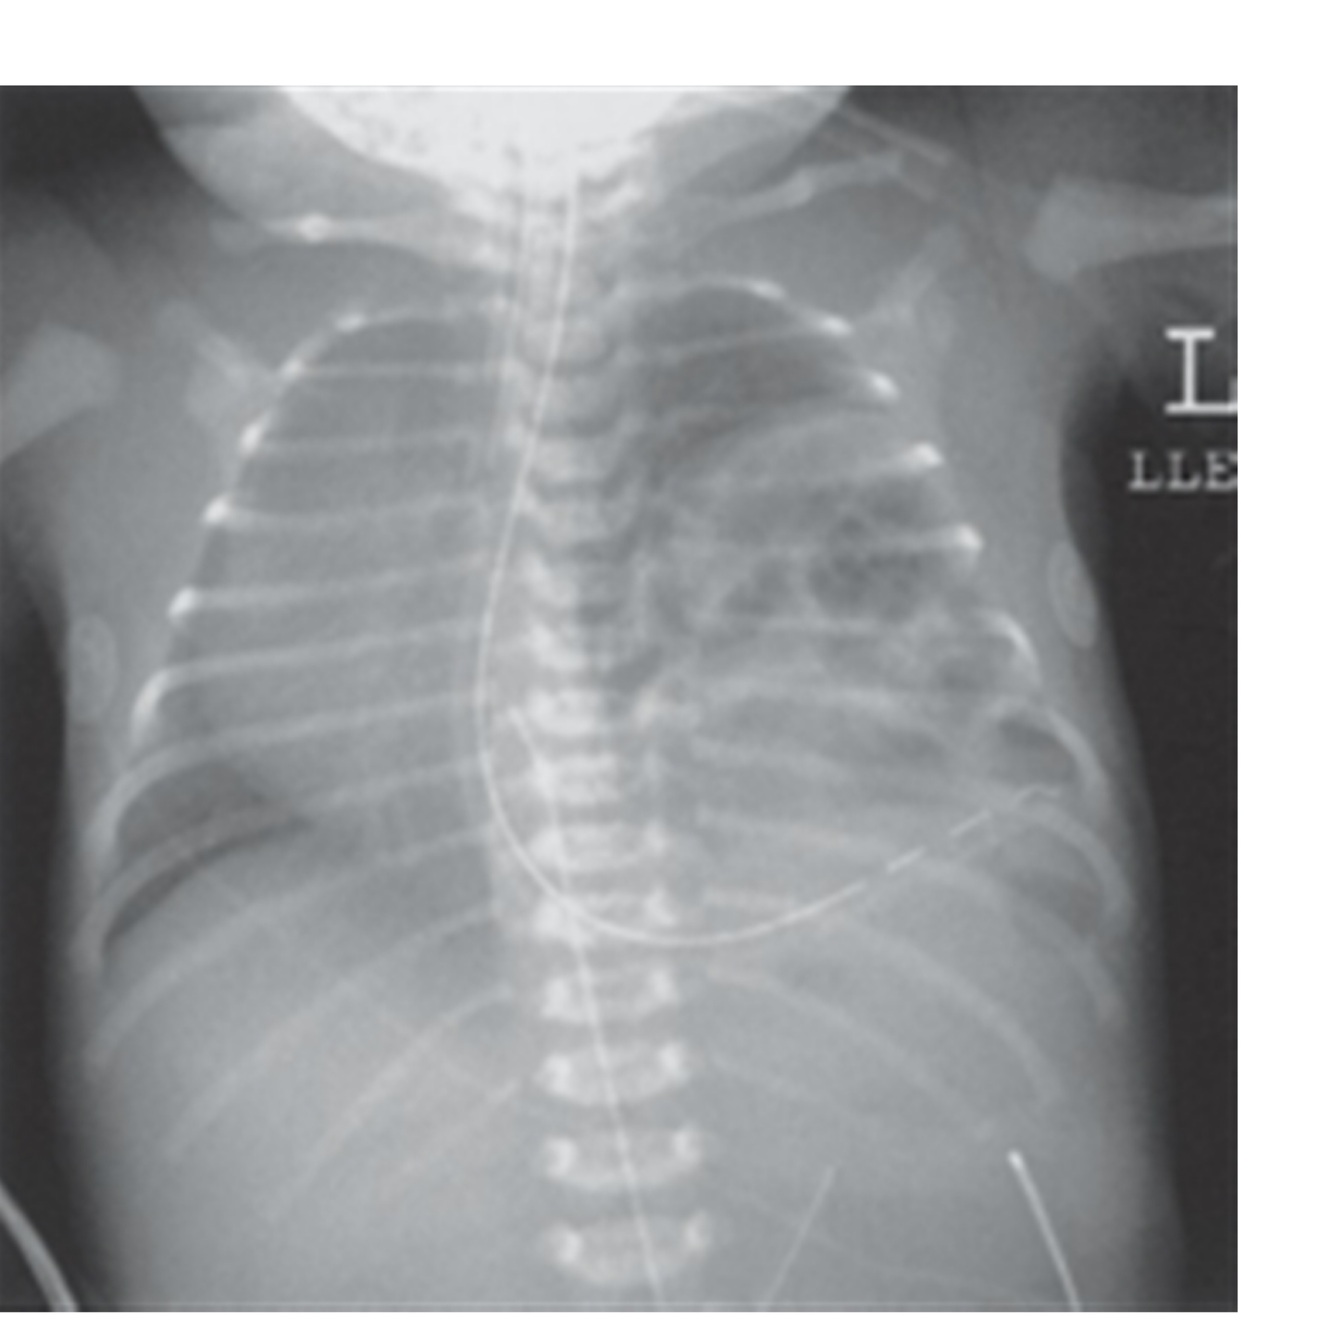

121

Diagnóstico

Hérnia diafragmática

122